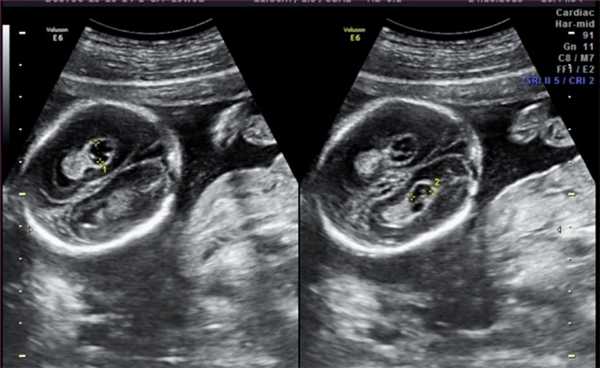

4. Гиперэхогенный фокус в желудочке сердца.

Это термин, говорящий о повышенной эхогенности (яркости) небольшого участка сердечной мышцы на ультразвуковом изображении. Выявление гиперэхогенного фокуса в сердце НЕ является пороком развития сердца, а просто отражает характер его ультразвукового изображения. Гиперэхогенный фокус возникает в месте повышенного отложения солей кальция на одной из мышц сердца, что не мешает нормальной работе сердца плода и не требует никакого лечения.

Почему у плода может выявляться гиперэхогенный фокус в сердце?

Иногда гиперэхогенный фокус в сердце выявляется у абсолютно нормальных плодов, и при УЗИ в динамике этот признак может исчезать. Наличие гиперэхогенного фокуса в сердце плода может быть проявлением хромосомных болезней плода, в частности, синдрома Дауна. В связи с этим при обнаружении гиперэхогенного фокуса проводится тщательная оценка анатомии плода. Однако этот маркер относится к «малым» маркерам синдрома Дауна, поэтому выявление только гиперэхогенного фокуса в сердце не повышает риск наличия синдрома Дауна и не является показанием к проведению других диагностических процедур.

Что делать при выявлении гиперэхогенного фокуса в сердце плода?

Если у плода выявлен ТОЛЬКО гиперэхогенный фокус в сердце, то никаких дополнительных обследований не требуется; риск болезни Дауна не увеличивается. На плановом УЗИ в 32-34 недели еще раз будет осмотрено сердце плода. В большинстве случаев гиперэхогенный фокус в сердце исчезает к этому сроку беременности, но даже если он продолжает оставаться в сердце, это никак не влияет на здоровье плода и тактику ведения беременности.